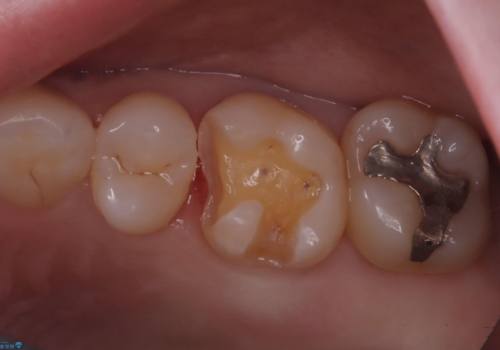

保険適用のメタルインレーと歯質の境目が、歯質が欠けてしまったのか大きなくぼみ汚れが停滞しやすい状態になっていました。歯冠色材料でのやり替えを希望されたため、セラミックインレーでのやり替えとなりました。

左上6番に入っている保険適応のメタルインレーと歯質との境目(近心側室エリア)に不適部位を認め、そのくぼみに汚れが停滞しやすい状態となっていました。

適合性・審美性を考慮し、セラミックインレーでのやり替えとなりました。